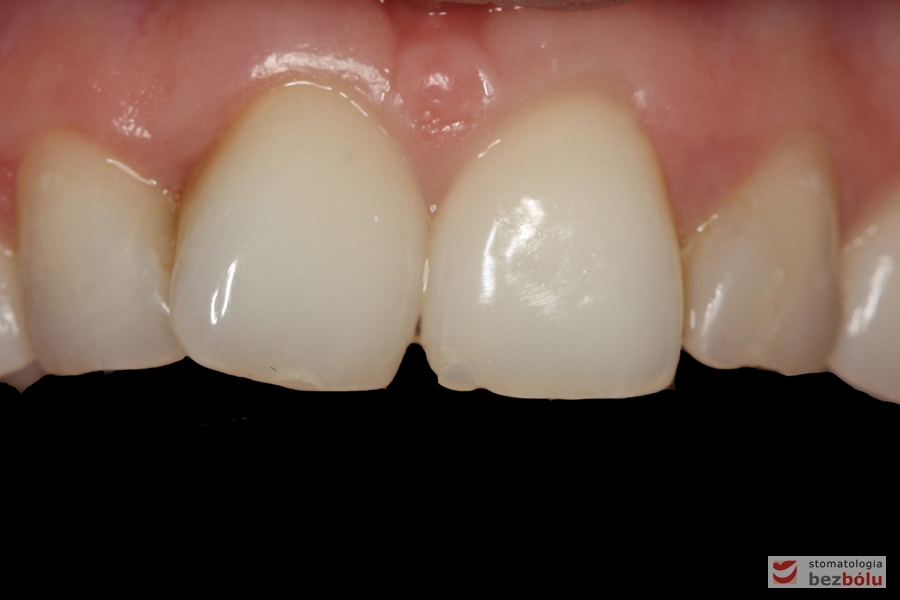

Ostateczne licówki caoceramiczne osadzone na zębach w odcinku przednim

Zmiana relacji długości do szerokości - zbliżenie do normy idealnych proporcji =80%

Zmiana relacji długości do szerokości – zbliżenie do normy idealnych proporcji =80%